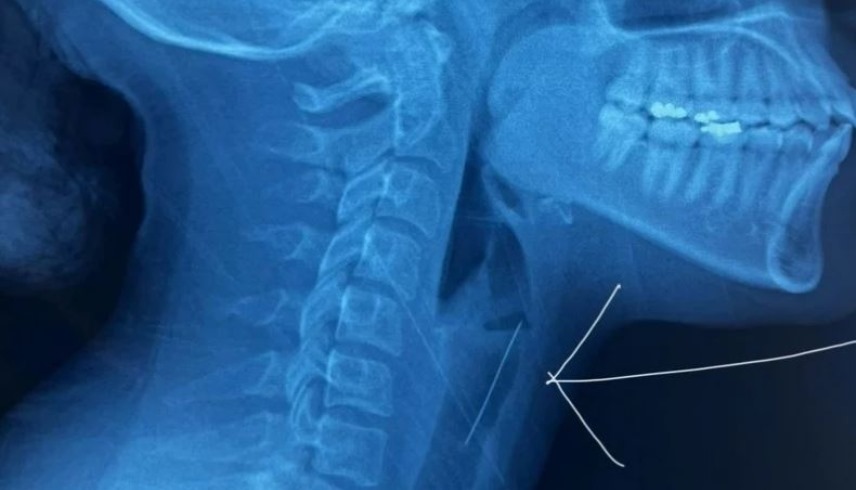

وأظهرت الفحوص الطبية، والأشعة المقطعية، أن الدبوس استقر في حنجرتها، ما استلزم تدخلاً جراحياً دقيقاً لإزالته.

وعلى الفور، باشر الطاقم الطبي بالمستشفى استخراج الدبوس بمنظار حنجري متطور، وبمساعدة كاميرا دقيقة مكّنت الفريق من إزالة الدبوس دون إلحاق ضرر بالحلق أو القصبة الهوائية.